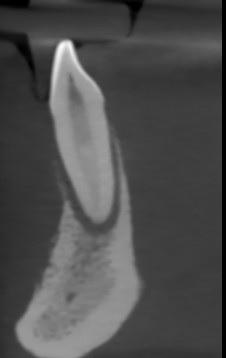

Obraz radiologiczny ukazuje zmiany w przednim odcinku kości żuchwy obejmujące kość części zębodołowej w okolicy zębów 33-43 oraz zmiany w kości spojenia żuchwy.

W kości przyzębia obserwowane częściowa resorpcja blaszki zbitej zębodołu.

Wyraźne poszerzenie ozębnej brzeżnej.

Niszczenie rozpoczyna się w połowie długości korzeni zębów i biegnie w kierunku brzegu wyrostka.

Obraz destrukcji kostnej jak w przebiegu agresywnego zapalenia przyzębia.